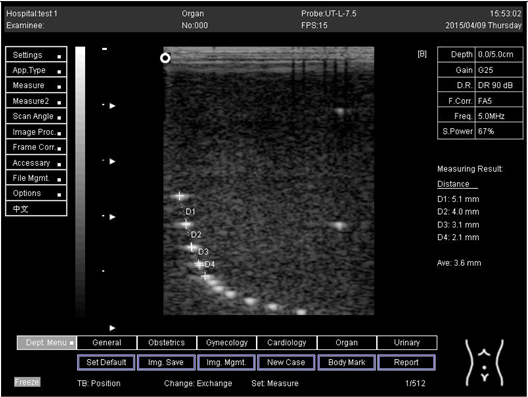

9.0 Axial resolution

Biomimetics 07 00130 i009

D1 = 5.0

D2 = 3.9

D3 = 3.0

D4 = 2.2

Lateral resolution

Biomimetics 07 00130 i010

D1 = 4.9

D2 = 4.1

D3 = 2.9

D4 = 2.0